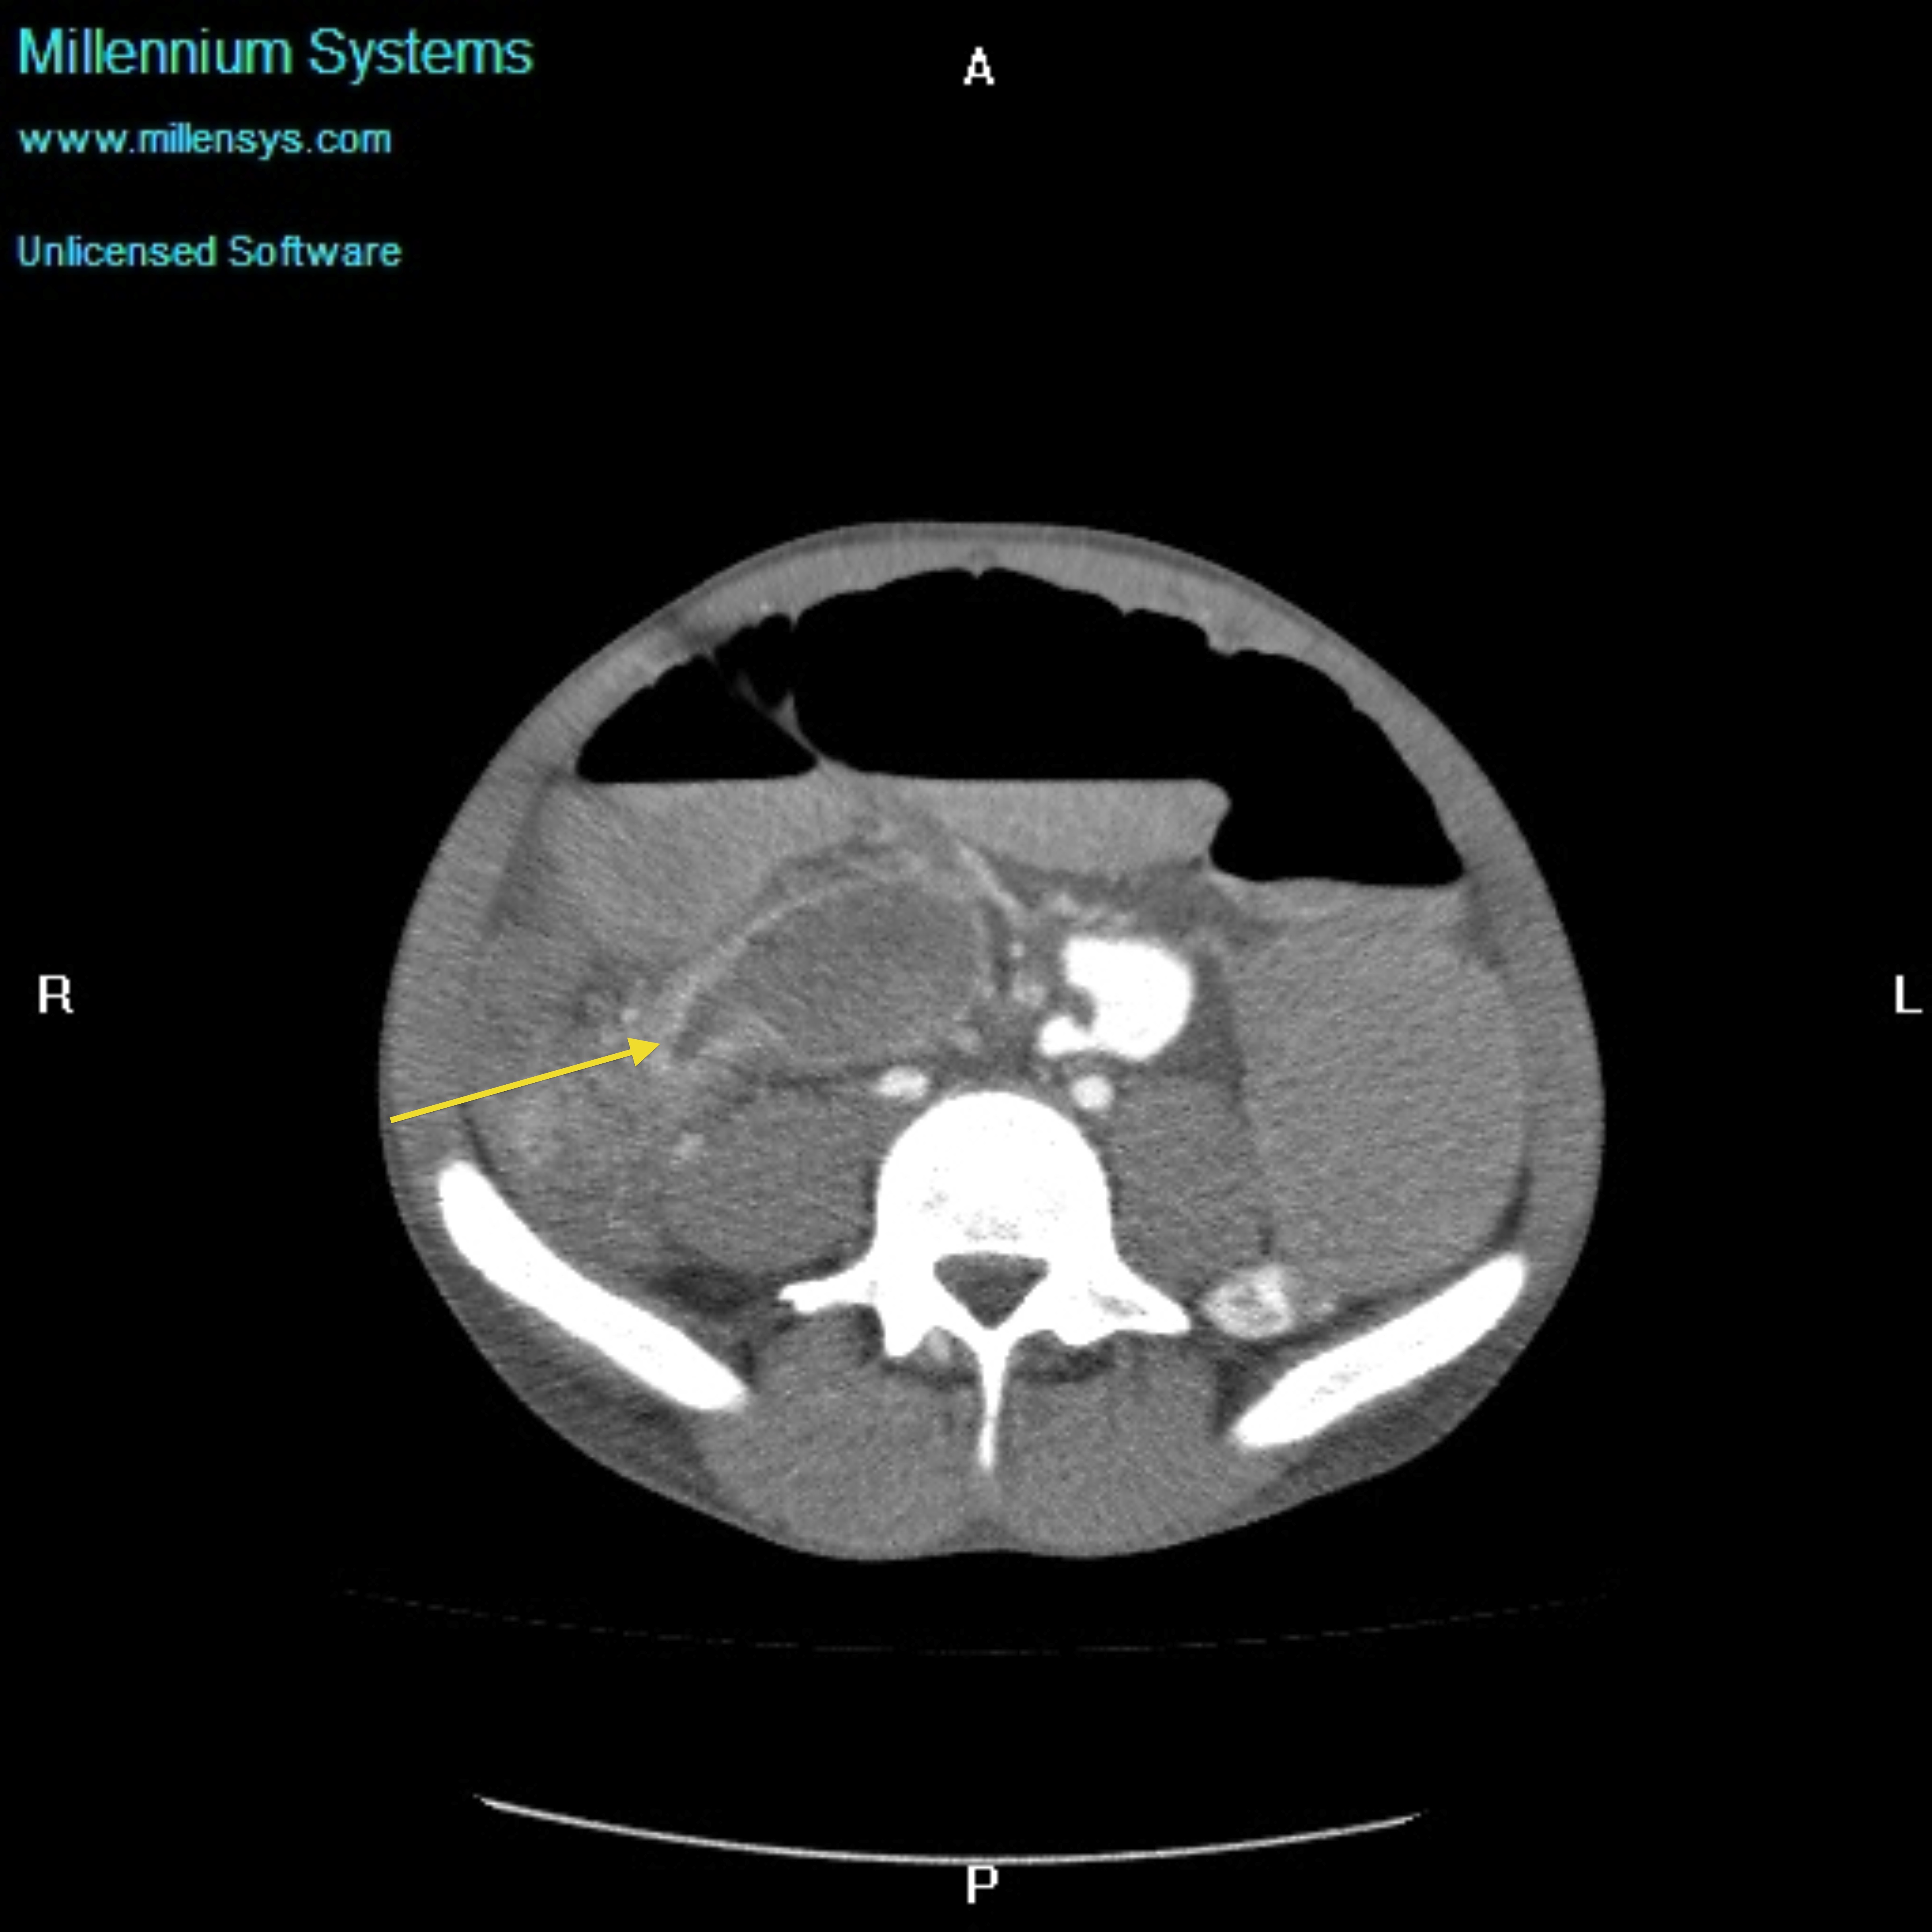

Small bowel obstruction is a common clinical presentation that presents a diagnostic conundrum. Over the last 2 decades, there has been a paradigm shift in the radiological investigation of small bowel obstruction (SBO) and in the indication for and timing of surgical intervention. Cross sectional imaging (predominantly computed tomography) has largely replaced the widespread use of radiographic small bowel follow-through studies as the imaging modality of choice for SBO. This article illustrates the current imaging modalities available for diagnosis of small bowel obstruction. (Full text available online at www.medpharm.tandfonline.com/ojfp) S Afr Fam Pract 2015; DOI: /10.1080/20786190.2014.977052